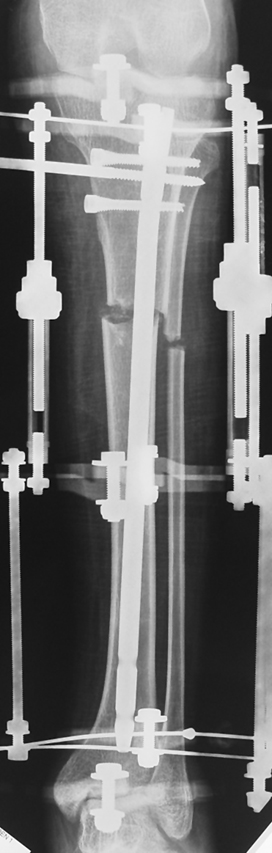

3. POSTTRAUMATIC LOWER LIMB SHORTNESS (MALUNION)

This type of shortness occurs after a fracture heals in a shortened position. Most cases are seen in adults and can be treated with one lengthening operation. Additional deformities can be corrected simultaneously. Most of these cases can be treated with lengthening over nail or just corrections and intramedullary nailing.